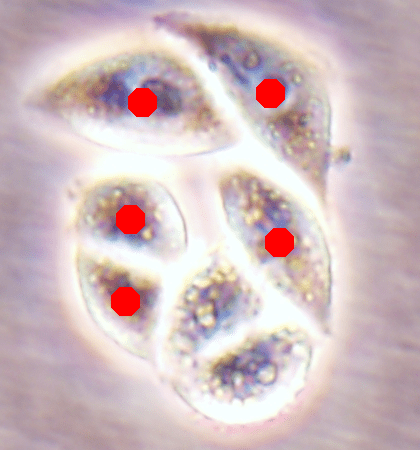

Before the advances in deep learning, the traditional approach for cell detection/segmentation is to employ low-level handcrafted features, reflecting color, edge, and shape characteristics of cells. This approach has given promising results when the features are defined properly, as a good representation of the visual cell characteristics. On the other hand, these characteristics may change from one cell type to another (see Fig. 1) and new features need to be defined to meet the cell characteristics of a new type. Additionally, when there exists heterogeneity in the visual characteristics of the same cell type, using a single model may not be sufficient to detect all cells of this type, particularly for cancer cells which are exploited more in high throughput screening.

![]() |

| (a) | (b) | (c) |

We test our DeepDistance model on three datasets, each of which consists of live cell images of a different cell line. They are the CAMA-1, MDA-MB-453, and MDA-MB-468 human breast cancer cell lines. The images in all datasets were acquired at magnification and pixel resolution. An example image from each dataset is shown in Fig. 1. As seen in this figure, cells might be visually different within and across different cell lines.